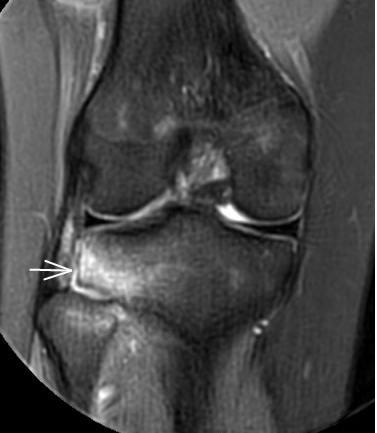

2. 運動后“打軟腿”——韌帶的“斷弦危機(jī)”

場景:打球急停后膝蓋不穩(wěn),走路像“踩棉花”

MRI偵查:揪出前交叉韌帶斷裂(呈“波浪狀”或連續(xù)性中斷)、內(nèi)側(cè)副韌帶損傷,防止關(guān)節(jié)“脫軌”

(內(nèi)側(cè)副韌帶損傷)